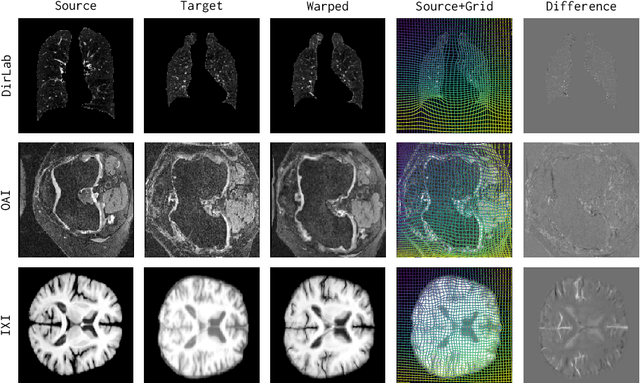

Abstract:Modern medical image registration approaches predict deformations using deep networks. These approaches achieve state-of-the-art (SOTA) registration accuracy and are generally fast. However, deep learning (DL) approaches are, in contrast to conventional non-deep-learning-based approaches, anatomy-specific. Recently, a universal deep registration approach, uniGradICON, has been proposed. However, uniGradICON focuses on monomodal image registration. In this work, we therefore develop multiGradICON as a first step towards universal *multimodal* medical image registration. Specifically, we show that 1) we can train a DL registration model that is suitable for monomodal *and* multimodal registration; 2) loss function randomization can increase multimodal registration accuracy; and 3) training a model with multimodal data helps multimodal generalization. Our code and the multiGradICON model are available at https://github.com/uncbiag/uniGradICON.

Abstract:Conventional medical image registration approaches directly optimize over the parameters of a transformation model. These approaches have been highly successful and are used generically for registrations of different anatomical regions. Recent deep registration networks are incredibly fast and accurate but are only trained for specific tasks. Hence, they are no longer generic registration approaches. We therefore propose uniGradICON, a first step toward a foundation model for registration providing 1) great performance \emph{across} multiple datasets which is not feasible for current learning-based registration methods, 2) zero-shot capabilities for new registration tasks suitable for different acquisitions, anatomical regions, and modalities compared to the training dataset, and 3) a strong initialization for finetuning on out-of-distribution registration tasks. UniGradICON unifies the speed and accuracy benefits of learning-based registration algorithms with the generic applicability of conventional non-deep-learning approaches. We extensively trained and evaluated uniGradICON on twelve different public datasets. Our code and the uniGradICON model are available at https://github.com/uncbiag/uniGradICON.